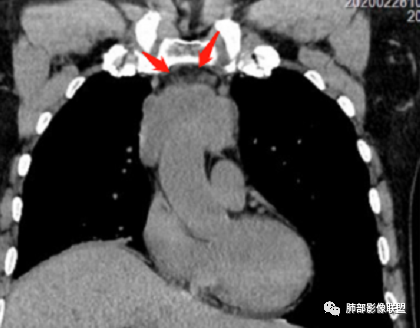

男性患者,65岁,前胸后背疼痛一个月。胸部影像:前上纵隔分叶状的软组织肿块,形态不规则,包绕大血管生长趋势,与周围分界不清,密度较均匀,呈多结节融合,肿块周围可见肿大淋巴结,内乳动脉旁淋巴结大,上腔受累,肿物内可见低密度区,增强扫描周围轻度强化。考虑:恶性病变,淋巴瘤?胸腺神经内分泌肿瘤?鉴别胸腺瘤

内乳淋巴结

我记得黄勇老师的课件提到:内乳淋巴结、钙化有价值。

中老年男性,前纵隔占位,基本居中,向两侧生长;边缘膨隆分叶,部分边界不清,增强不均匀轻中度强化,坏死区边界不清;周围多发增大淋巴结,考虑恶性。主要在胸腺癌、胸腺瘤、淋巴瘤之间鉴别。病灶偏软,有钻缝样生长,这些征象偏向于淋巴瘤。但此例老年患者,病灶内有点状钙化,缺乏结节堆砌感,倾向胸腺癌诊断。